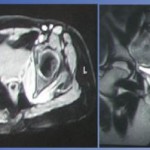

Over 5 months, he continued to functionally decline and was mostly bedbound. He was re-admitted due to a fall secondary to lower limb weakness, right worse than left. Physical examination revealed right lower limb shortening and limited hip ranging with mild tenderness. X-rays revealed right hip destruction involving the superior acetabulum with superior subluxation and left hip degenerative changes (Fig. 3). An orthopedic review was requested and magnetic resonance imaging (MRI) of the pelvis and right hip showed evidence of bilateral hip effusion, worse on the right, with joint effusion partially decompressing into periarticular soft tissues (Fig. 4). In addition, there was acute osteomyelitis of the right acetabulum and femoral head with bony destruction and subluxation. Blood cultures grew pseudomonas aeruginosa. Ultrasound-guided right hip joint aspiration and core biopsy yielded no bacteria despite holding off antibiotics. Intravenous (IV) tazocin was started for pseudomonas bacteremia coverage.

2 months post-operatively, repeat MRI revealed interval progression of SA worse over the left hip (Fig. 5). Inflammatory markers remained raised with serum white blood cell count of 15.7× 109/L and C-reactive protein level of 28.6 mg/L. Interval X-rays showed left hip progressive destruction while the right hip remained grossly stable since last discharge (Fig. 6). He was re-admitted for repeat bilateral hip joint washout, synovectomy debridement and a 1.5-stage antibiotic-loaded THA with CUMARS through ABMS approach in a single setting. An anterior-based approach was chosen to preserve soft tissue and muscle and reduce the risk of dislocation after THA. The surgery was performed under general anesthesia in lateral decubitus position. Intra-operative right hip findings include recalcitrant SA and osteomyelitis with synovitis and no purulent fluid, false acetabulum with Paprosky 3A bone loss, and subluxation more than 3 cm. Meanwhile, intra-operative left hip findings include SA with synovitis with no purulent fluid, deformed and unhealthy femoral head, and superolateral acetabular wall containing bone loss with superior wall intact. The damaged femoral head and neck were excised. Meticulous and radical debridement was performed to remove remnant infective tissues. The acetabulum was debrided using an acetabular reamer. Five tissues from each side were taken and sent for culture. Before reconstruction, the surgical site was re-draped and surgical team re-gowned with new sets of surgical instruments. The articulating spacers for the right hip were prepared using a Stryker RimFit cup 50 mm OD 32 mm ID, Stryker LFIT V40 femoral head 32 mm OD, +4 offset, and Exeter V40 cemented hip stem 35.5 offset stem length 125 mm stem length. The articulating spacers for the left hip were prepared using a Stryker RimFit cup 52 mm OD 36 mm ID, Stryker LFIT V40 femoral head 36mm OD, 0 offset, and Exeter V40 cemented hip stem 35.5 offset stem length 125 mm stem length (Stryker NY). 2g of ceftazidime was added to each packet of Palacos cement. Due to the significant amount of acetabulum bone loss for the right hip, an additional 2×3.5 cm cancellous screw was inserted to the superior acetabular wall defect. At the end of each section of the surgery, first being wound debridement and joint washout with subsequent 1.5-stage THA, the hip was irrigated with copious amounts of normal saline, chlorhexidine subsequently soaked in 9mls of 10% iodine mixed with 250 ml of normal saline. Intra-operative cultures revealed no bacterial growth. Post-operatively, he completed 2 more weeks of oral ciprofloxacin and was allowed to full weight bear immediately. However, his rehabilitation recovery was slow due to sarcopenia from prolonged functional decline and bedrest. On 1-month review, he was able to ambulate with walking frame with minimum assistance. There was no clinical or biochemical evidence of recurrent infection with serum white blood cell count of 9.1 × 109/L, C-reactive protein level of 0.9 mg/L. On 1-year review, he was he is able to ambulate with walking frame independently (Fig. 7) and there was no clinical evidence of infection recurrence. Overall, post-operative X-rays done on day 0, 1-month, and 1-year review revealed stable bilateral hip replacement prostheses with no evidence of periprosthetic fractures or loosening (Fig. 8).